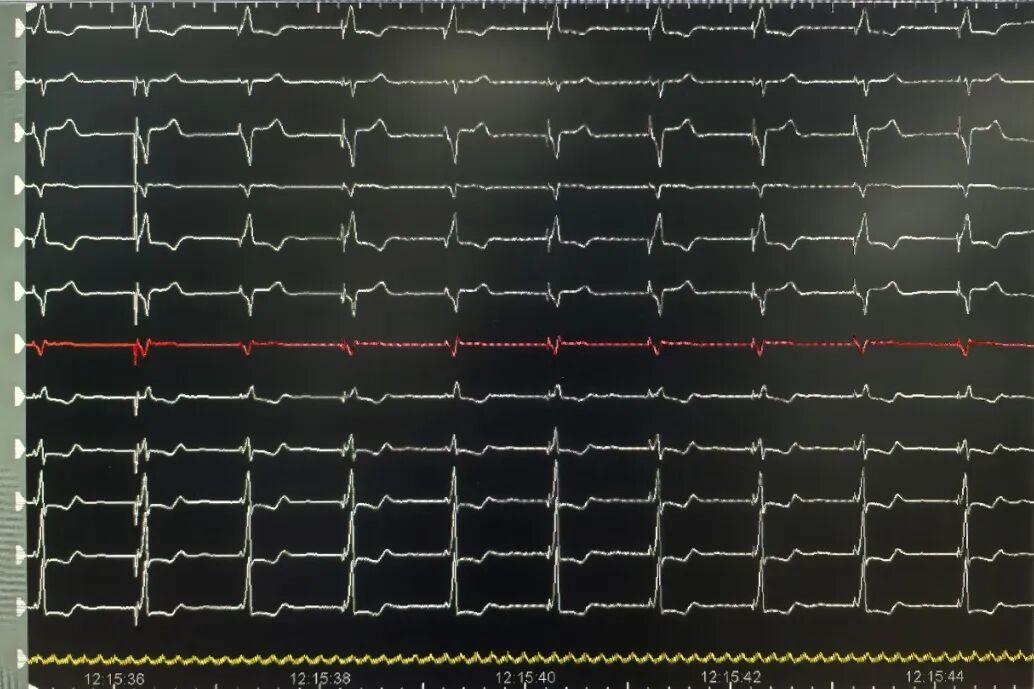

图3 手塑导丝3D间隔弯直接用普通心室螺旋电极行左束支起搏靶点图。可见左束支电位(P),P-V间期23ms;左室达峰时间86ms;起搏QRSd107ms;起搏阈值感知和阻抗分别为0.6V/0.4ms、

4mv和836Ω。走纸速度100mm/S.

图5 手塑导丝3D间隔弯直接用普通心室螺旋电极行左束支起搏术后12导联心电图,正常走纸速度25mm/S。从上到下分别肢体6导联和胸导联V1-6(红色为V1分界线)。